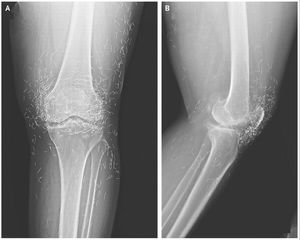

When doctors examined an X-ray image of the knees of a woman experiencing severe joint pain, they found a gold mine: hundreds of tiny gold acupuncture needles left in her tissue.The 65-year-old South Korean woman had previously been diagnosed with osteoarthritis, a condition in which the cartilage and bones within the joints degrade, causing pain and stiffness.But when pain relievers and anti-inflammatory drugs didn't alleviate the pain in her knees and only caused stomach discomfort, she had turned to acupuncture, she told her doctors. The needles, which were presumably made of gold, were intentionally left in her tissue for continued stimulation, her doctors wrote in the New England Journal of Medicine in December 2013.